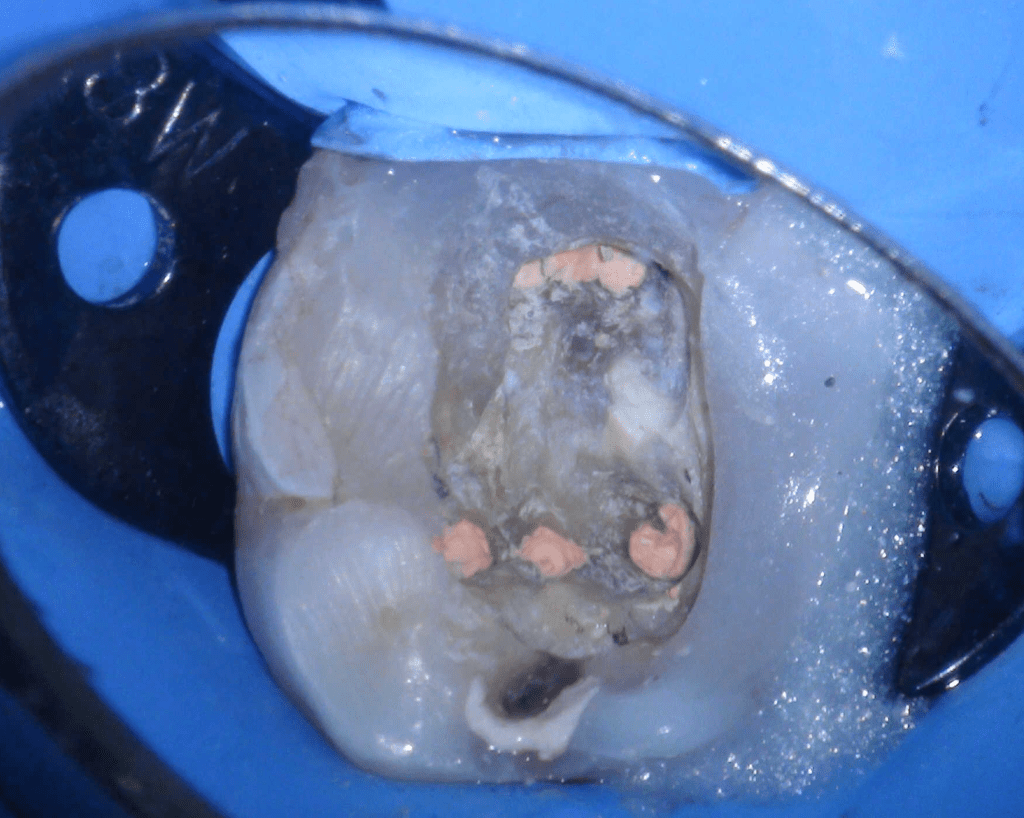

Reco preendo + 4 conductos molar superior